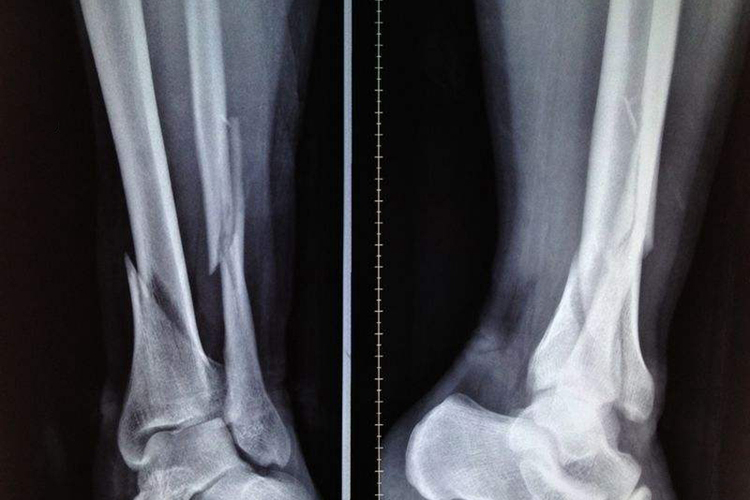

腓骨骨折临床愈合时间为2.5-3个月,因此正常情况下腓骨骨折3个月后可正常愈合。表现为骨折断端局部无压痛,无纵向叩击痛;骨折断端局部无异常活动(主动或被动);X线片显示骨折线模糊,有连线性骨痂通过骨析线,如骨折较轻或恢复较好,可显示骨小梁通过骨折线;在解除外固定的情况下,下肢能不扶拐在平地连续行走3分钟,并不少于30步。